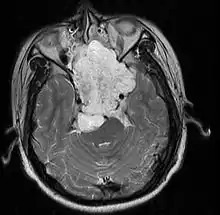

Chordomas can arise from bone in the skull base and anywhere along the spine. The two most common locations are cranially at the clivus and in the sacrum at the bottom of the spine.[2]